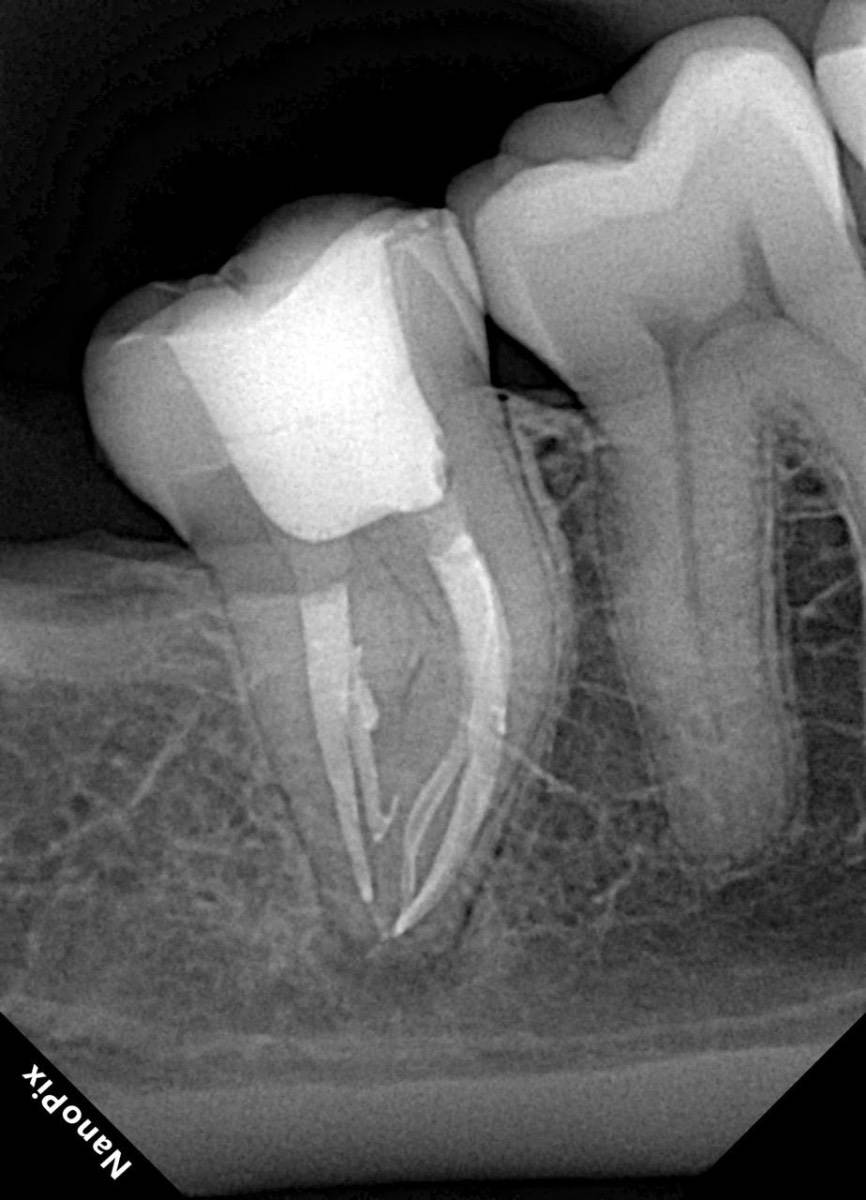

Гарриевич Опубликовано 31 января Автор Поделиться Опубликовано 31 января Когда в твоем кресле оказывается пациент с редким заболеванием «стоматолог-терапевт» работать всегда… легче. Именно! Потому что ты на 100% уверен, что этот человек понимает разницу между «гарантия» и «прогноз», а он на 100% уверен, что ты тот кто ему нужен. Зуб 4.7 со сложной анатомией, ступенькой в мезиальной системе, двойным изгибом, пропущенным каналом и апикальным периодонтитом. Реколл 1 год И сам осмотр через 1 год 4 1 1 Ссылка на комментарий

Гарриевич Опубликовано 18 марта Автор Поделиться Опубликовано 18 марта В 13.03.2026 в 15:26, Doc сказал: Круто! То, что вынимается, доктору вернуть надо или в металлолом сдать? :))) Обычно мы сдаем в чернмет, какие никакие деньги)) Реколл 3 года 1 Ссылка на комментарий